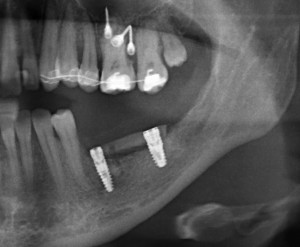

В настоящий момент производители выпускают линейки имплантов, предназначенных для установки в лунку только что удаленного зуба. Они отличаются крупной агрессивной резьбой, назначение которой – обеспечить качественную стабилизацию импланта в условиях лунки только что удаленного зуба.